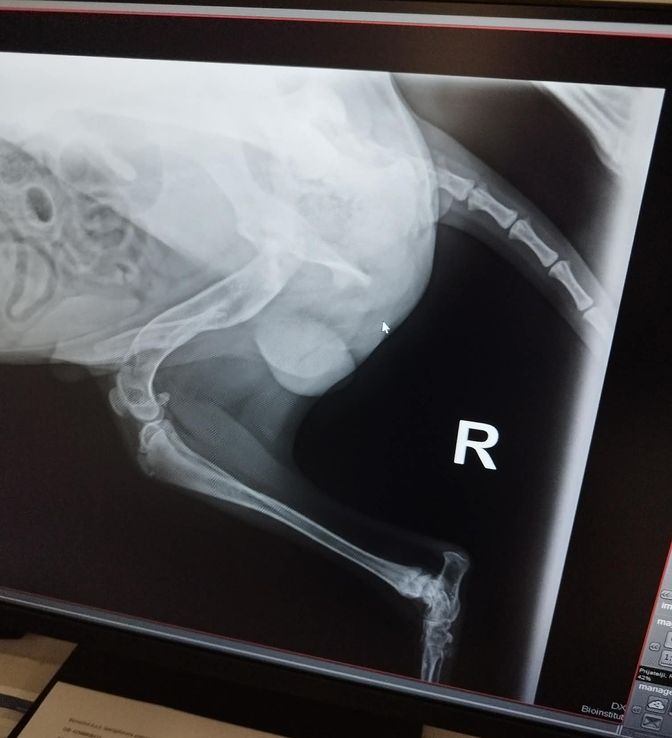

Wir wissen momentan, dass er aus einer Romasiedlung stammt. Er hat eine Verletzung an seinem rechten Hinterbeinchen. Davon wurden Röntgenbilder angefertigt, die in der Bildergalerie zu finden sind.